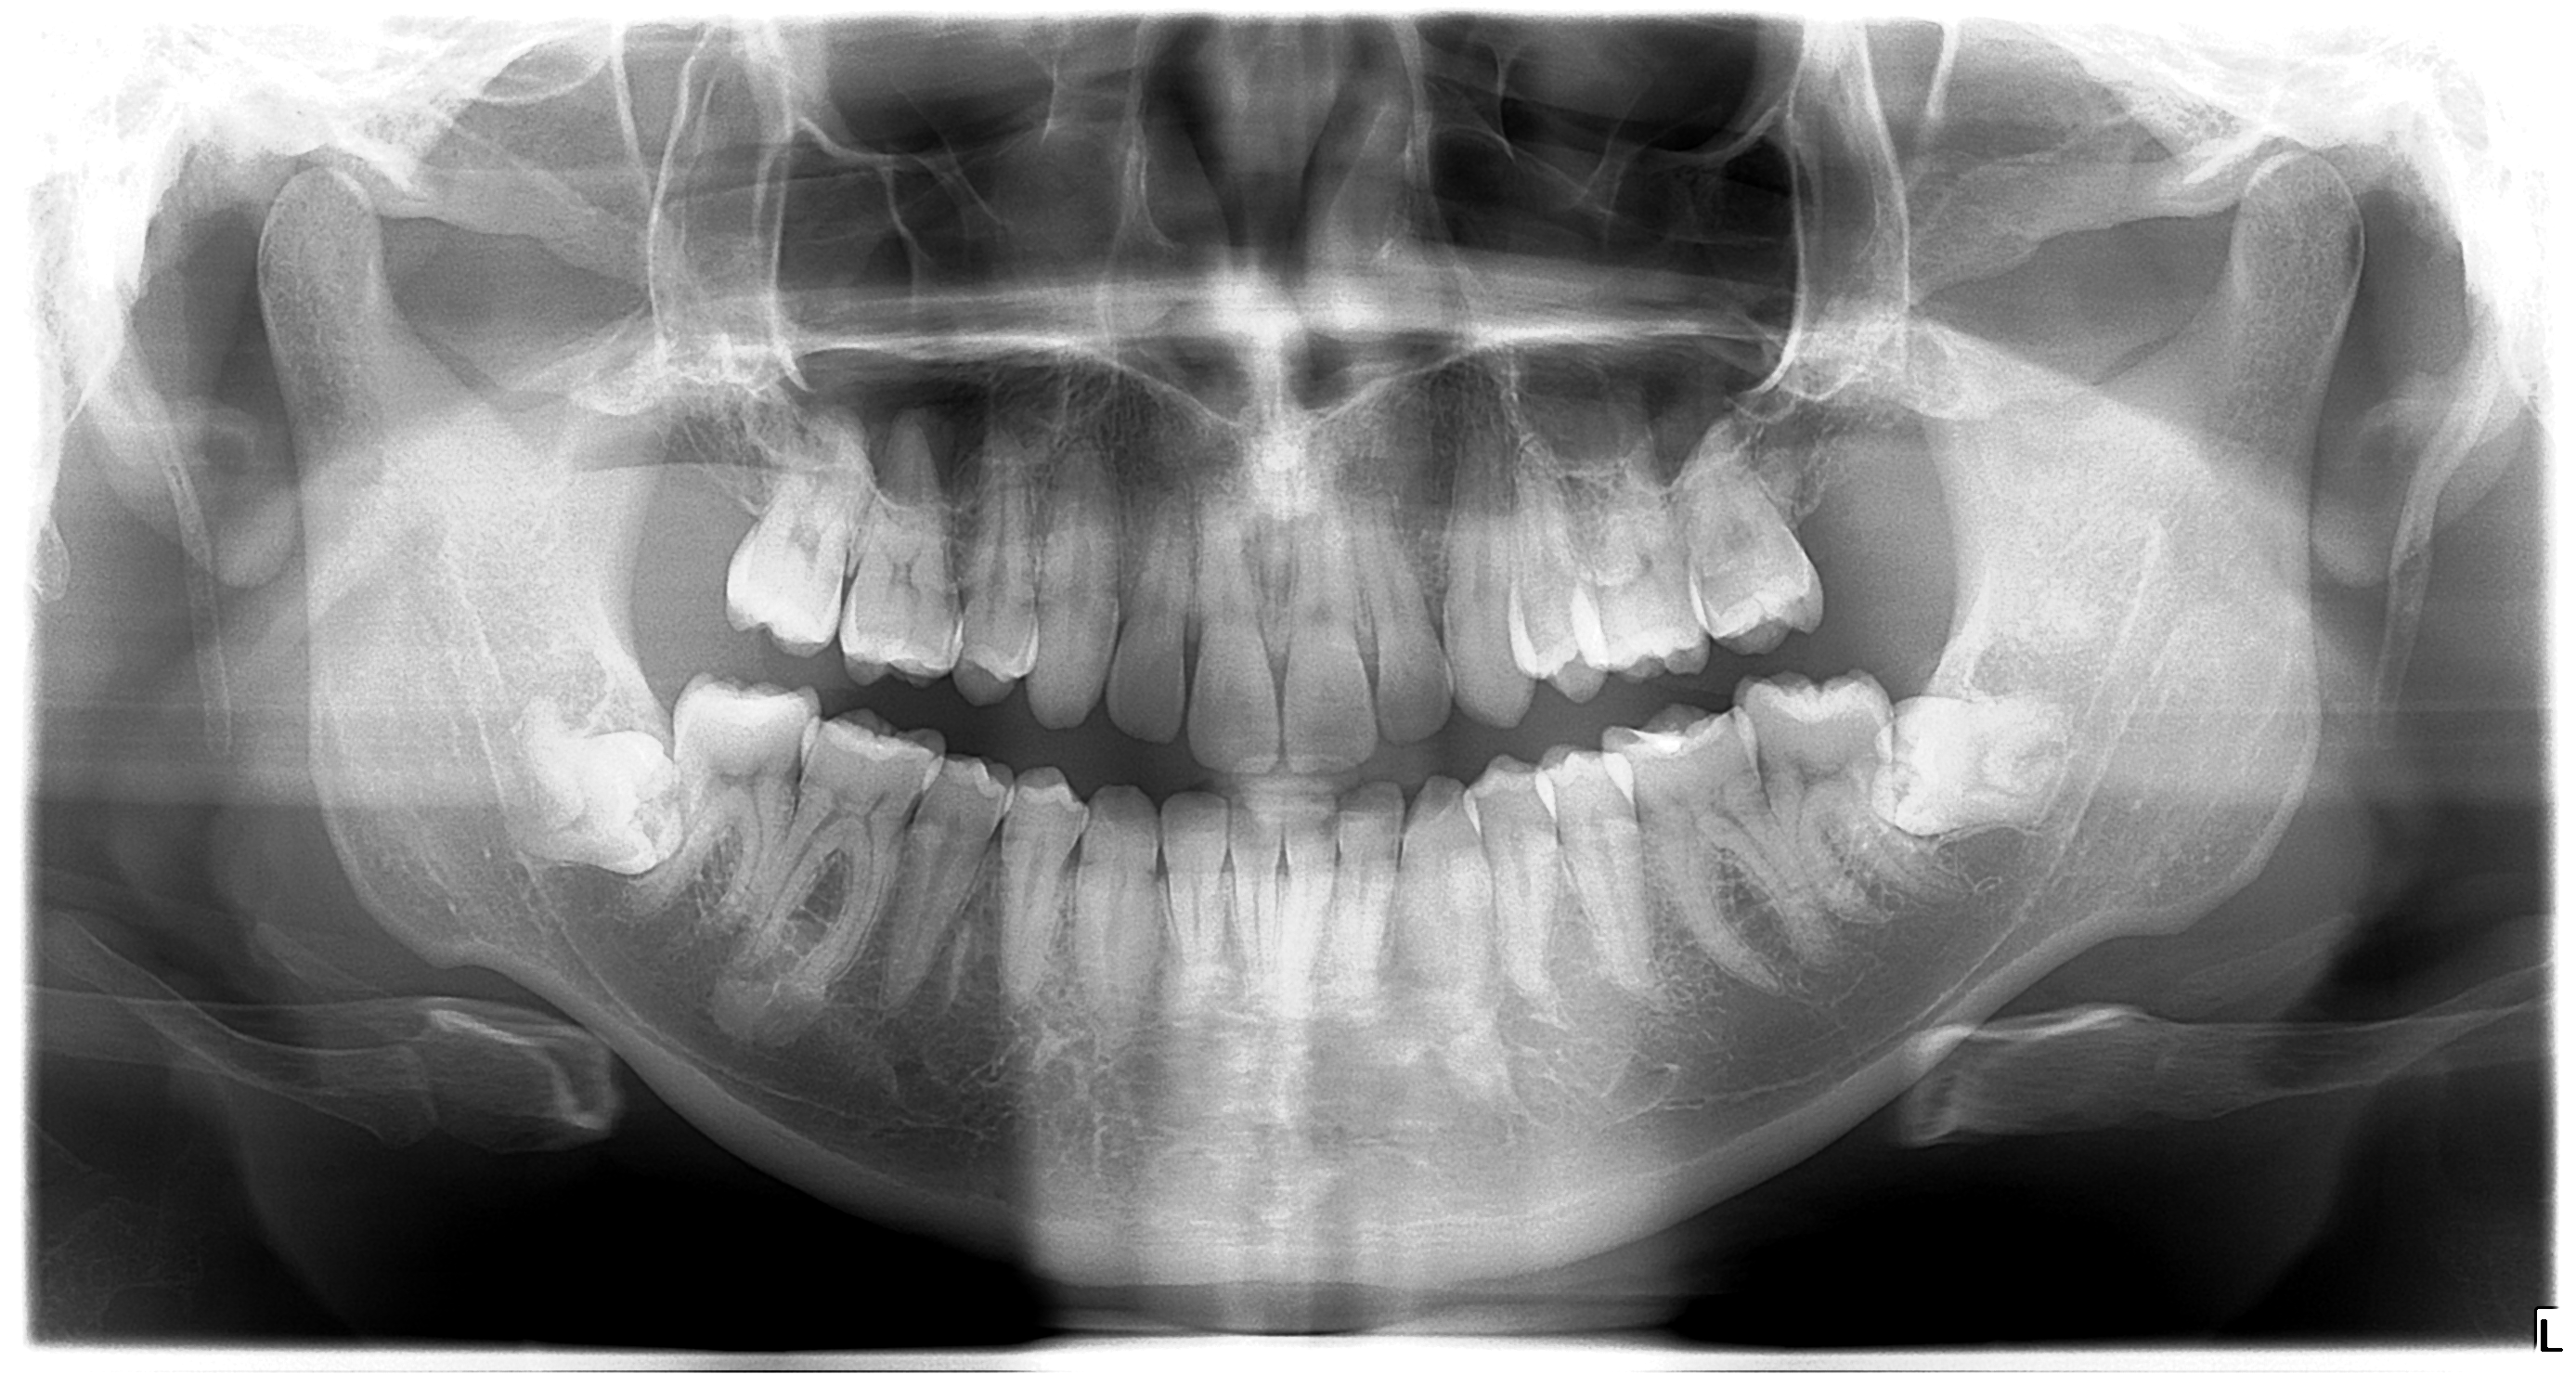

Fogeltávolítás